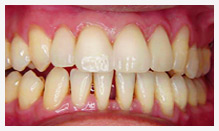

正常な歯肉

引締まったピンクの歯肉で出欠なし

歯周病の歯肉

ぷよぷよした歯肉で腫れ、出欠排膿